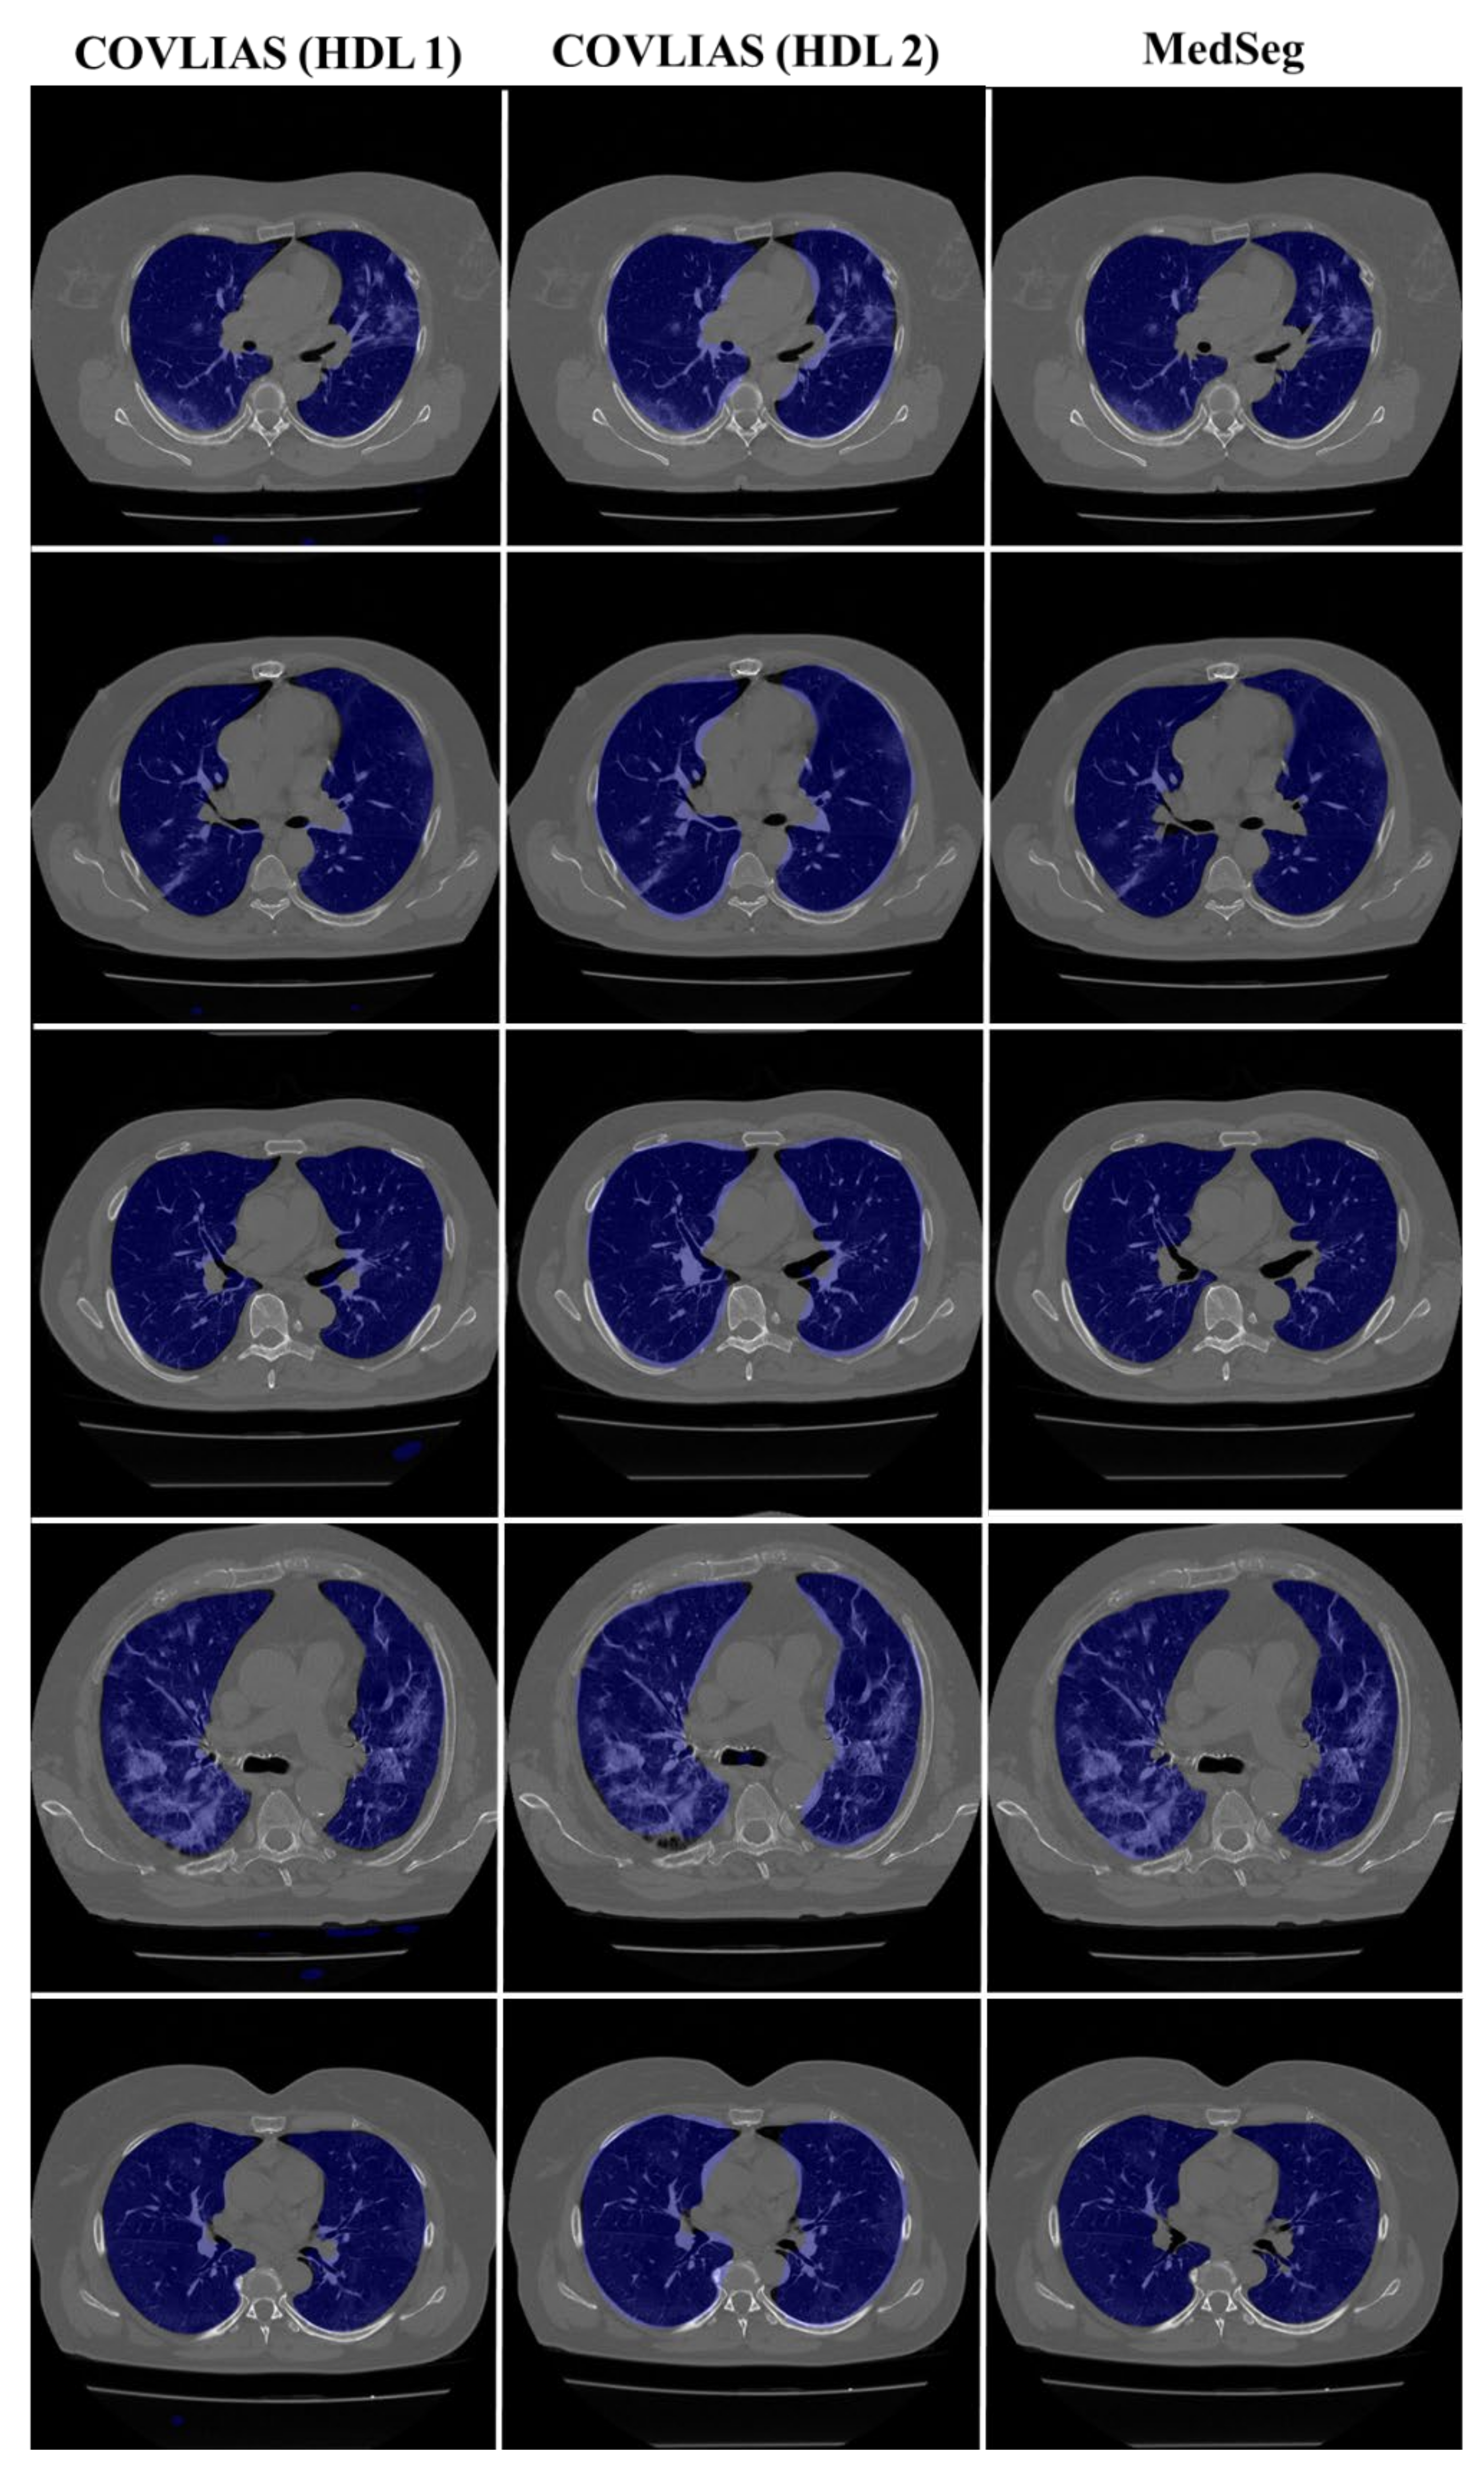

4.1. Performance: COVLIAS vs. MedSeg